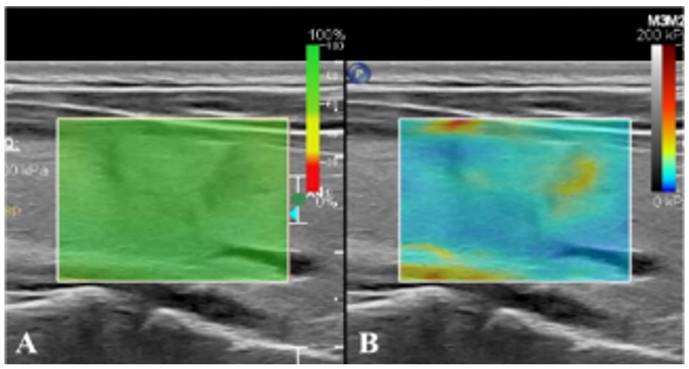

Real-time SWE method

After conventional ultrasonography was completed, the real-time SWE mode was switched to observe the hardness of lesions and surrounding tissues. Specifically, a 2 mm sampling frame was used to select the affected nodules and surrounding normal gland tissues as the region of interest. When the sampling frame displayed stable color without mosaic color points, the timer was started, with images saved dynamically (Figure 2). Then the elastic modulus value in the sampling frame was measured by Q-Box measurement software (Panotec, Italy). Measurement was repeated five times on the same lesion and the same section to take the average elasticity modulus (Eavg) and the ratio to that of surrounding normal tissues (Eratio).

Figure 2

Real-time SWE. (A) SWE image with reliability of 100%. (B) SWE mode showing that the hardness of nodules is greater than that of normal glands at the same depth.